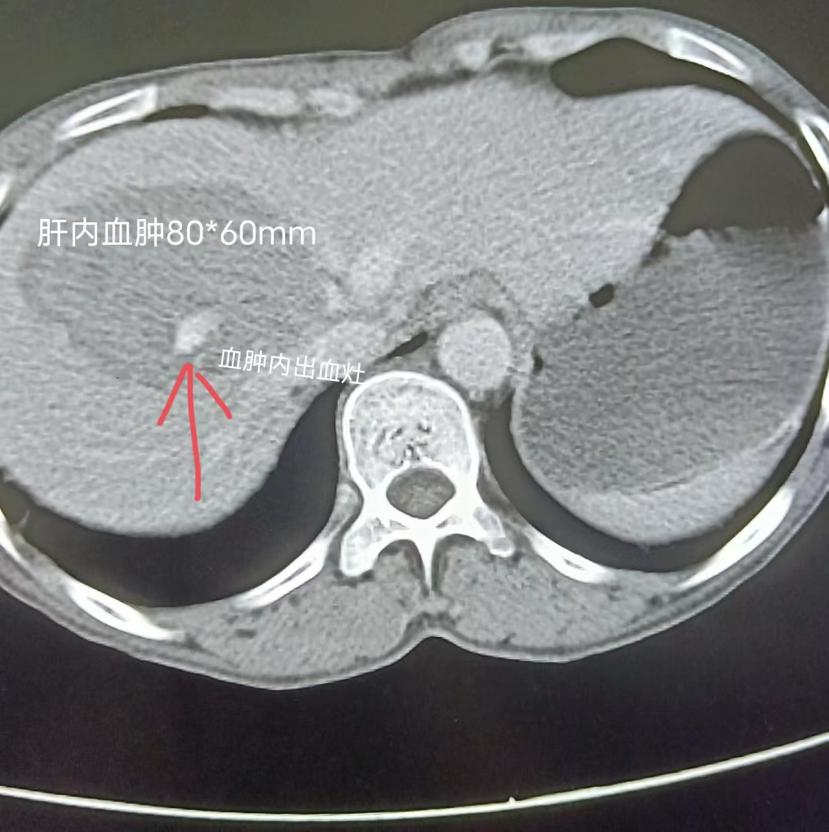

消毒、铺巾、穿刺、插管,有条不紊地进行着,行腹腔干造影,发现血管走形变异,尝试使用多种型号导管超选进入肝动脉困难。姚金顺主任及江张兵医师尝试用A型号导管挂住入口导丝深入后更换B型号导管终于成功进入肝固有动脉内,行DSA造影显示肝右叶分支动脉造影剂外溢,血液从破口向外流出,假性动脉瘤形成。为尽量多的保留患者的肝组织、保护其肝功能,采用同轴导管技术将微导管置入出血的肝动脉近端,经“三明治”栓塞法栓塞后成功将出血肝动脉栓塞,造影复查未见明显造影剂外溢,止血成功。手术顺利,患者无明显不适。